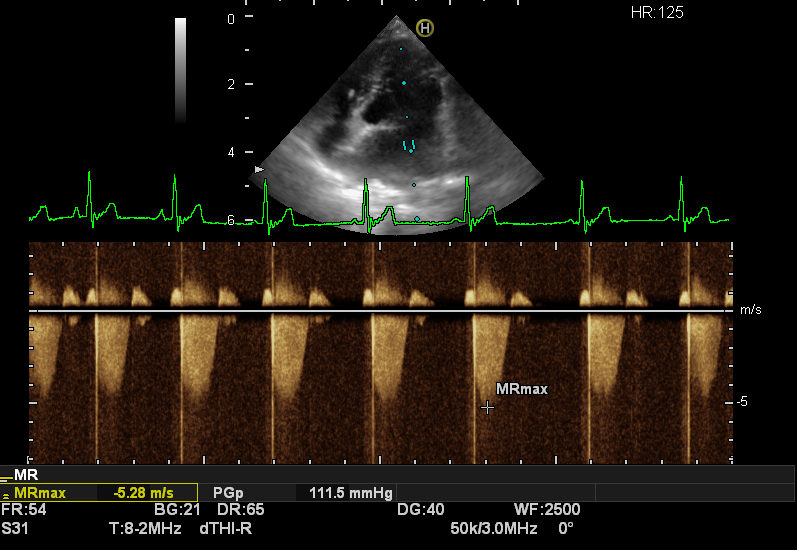

- Echocardiography (Heart Ultrasound): The gold standard for definitively identifying the disease and measuring heart chamber enlargement.

Congestive heart failure on the Right x-ray